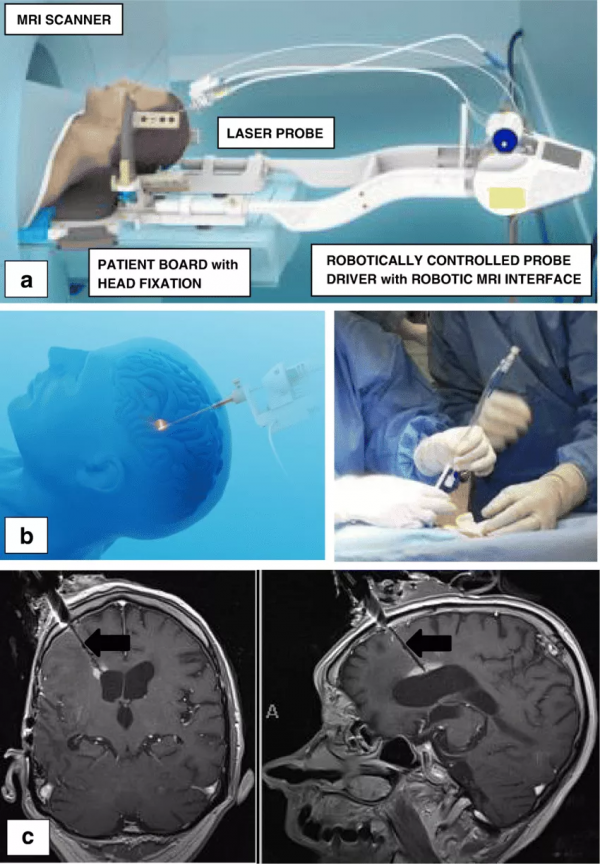

總而言之,LITT是具有廣泛應用前景的微創治療顱內病變的新方法。目前,在世界上的超過 100家知名的神經外科專業研究機構,LITT技術都正在得到越來越成熟的應用,比如James T. Rutka教授所在的世界水平兒童醫院之一加拿大多倫多大學兒童醫院 SickKids,該醫院是較早一批擁有完整LITT療法裝置的兒童醫院,其所採用的是Monteris Neuroblate系統,Rutka教授和他的團隊成員已能熟練運用這一微創技術治療小兒腦瘤和癲癇。

Monteris Neuroblate系統

對於LITT技術的運用,Rutka教授還曾總結了這項技術的三個關鍵要素:立體定向方法,將鐳射探針精確定位在治療目標內;手術鐳射系統隨時間變化的熱組織消融;MRI熱像儀可實時監測溫度變化和組織破壞。